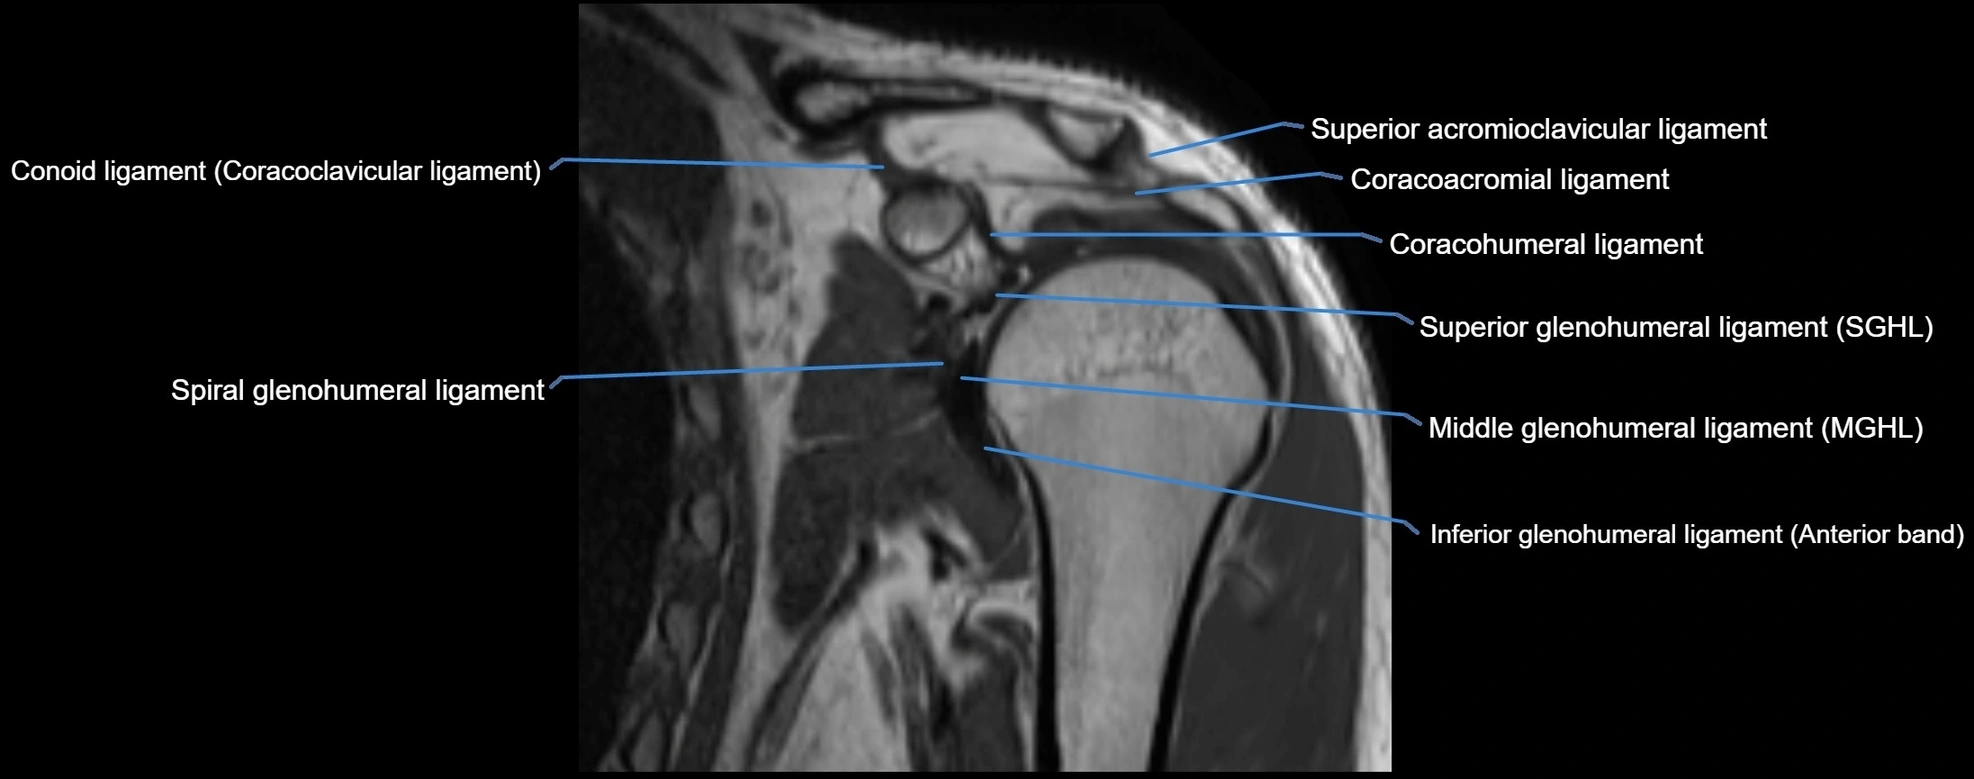

MRI images

image